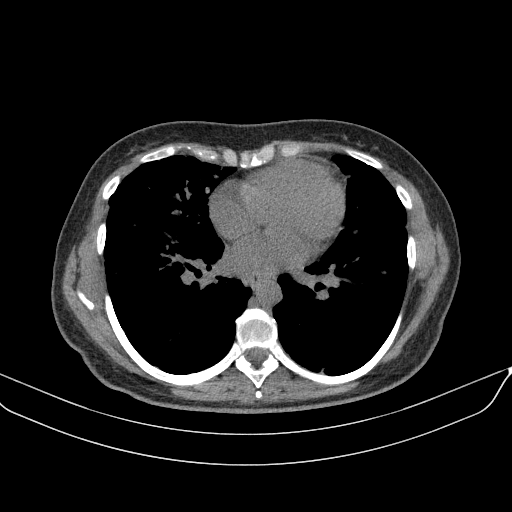

Image Grid

4Γ—3 grid: Rows show different image types (Original NATIVE, Reconstructed NATIVE, Original VENOUS, Generated VENOUS), Columns show windowing techniques (No Window, Lung Window, Mediastinum Window)

Original NATIVE CT scan (input)

Full window (WL 1023.5, WW 4095 β†’ Low βˆ’1024, High +3071)

Generated VENOUS CT scan (A→B translation)